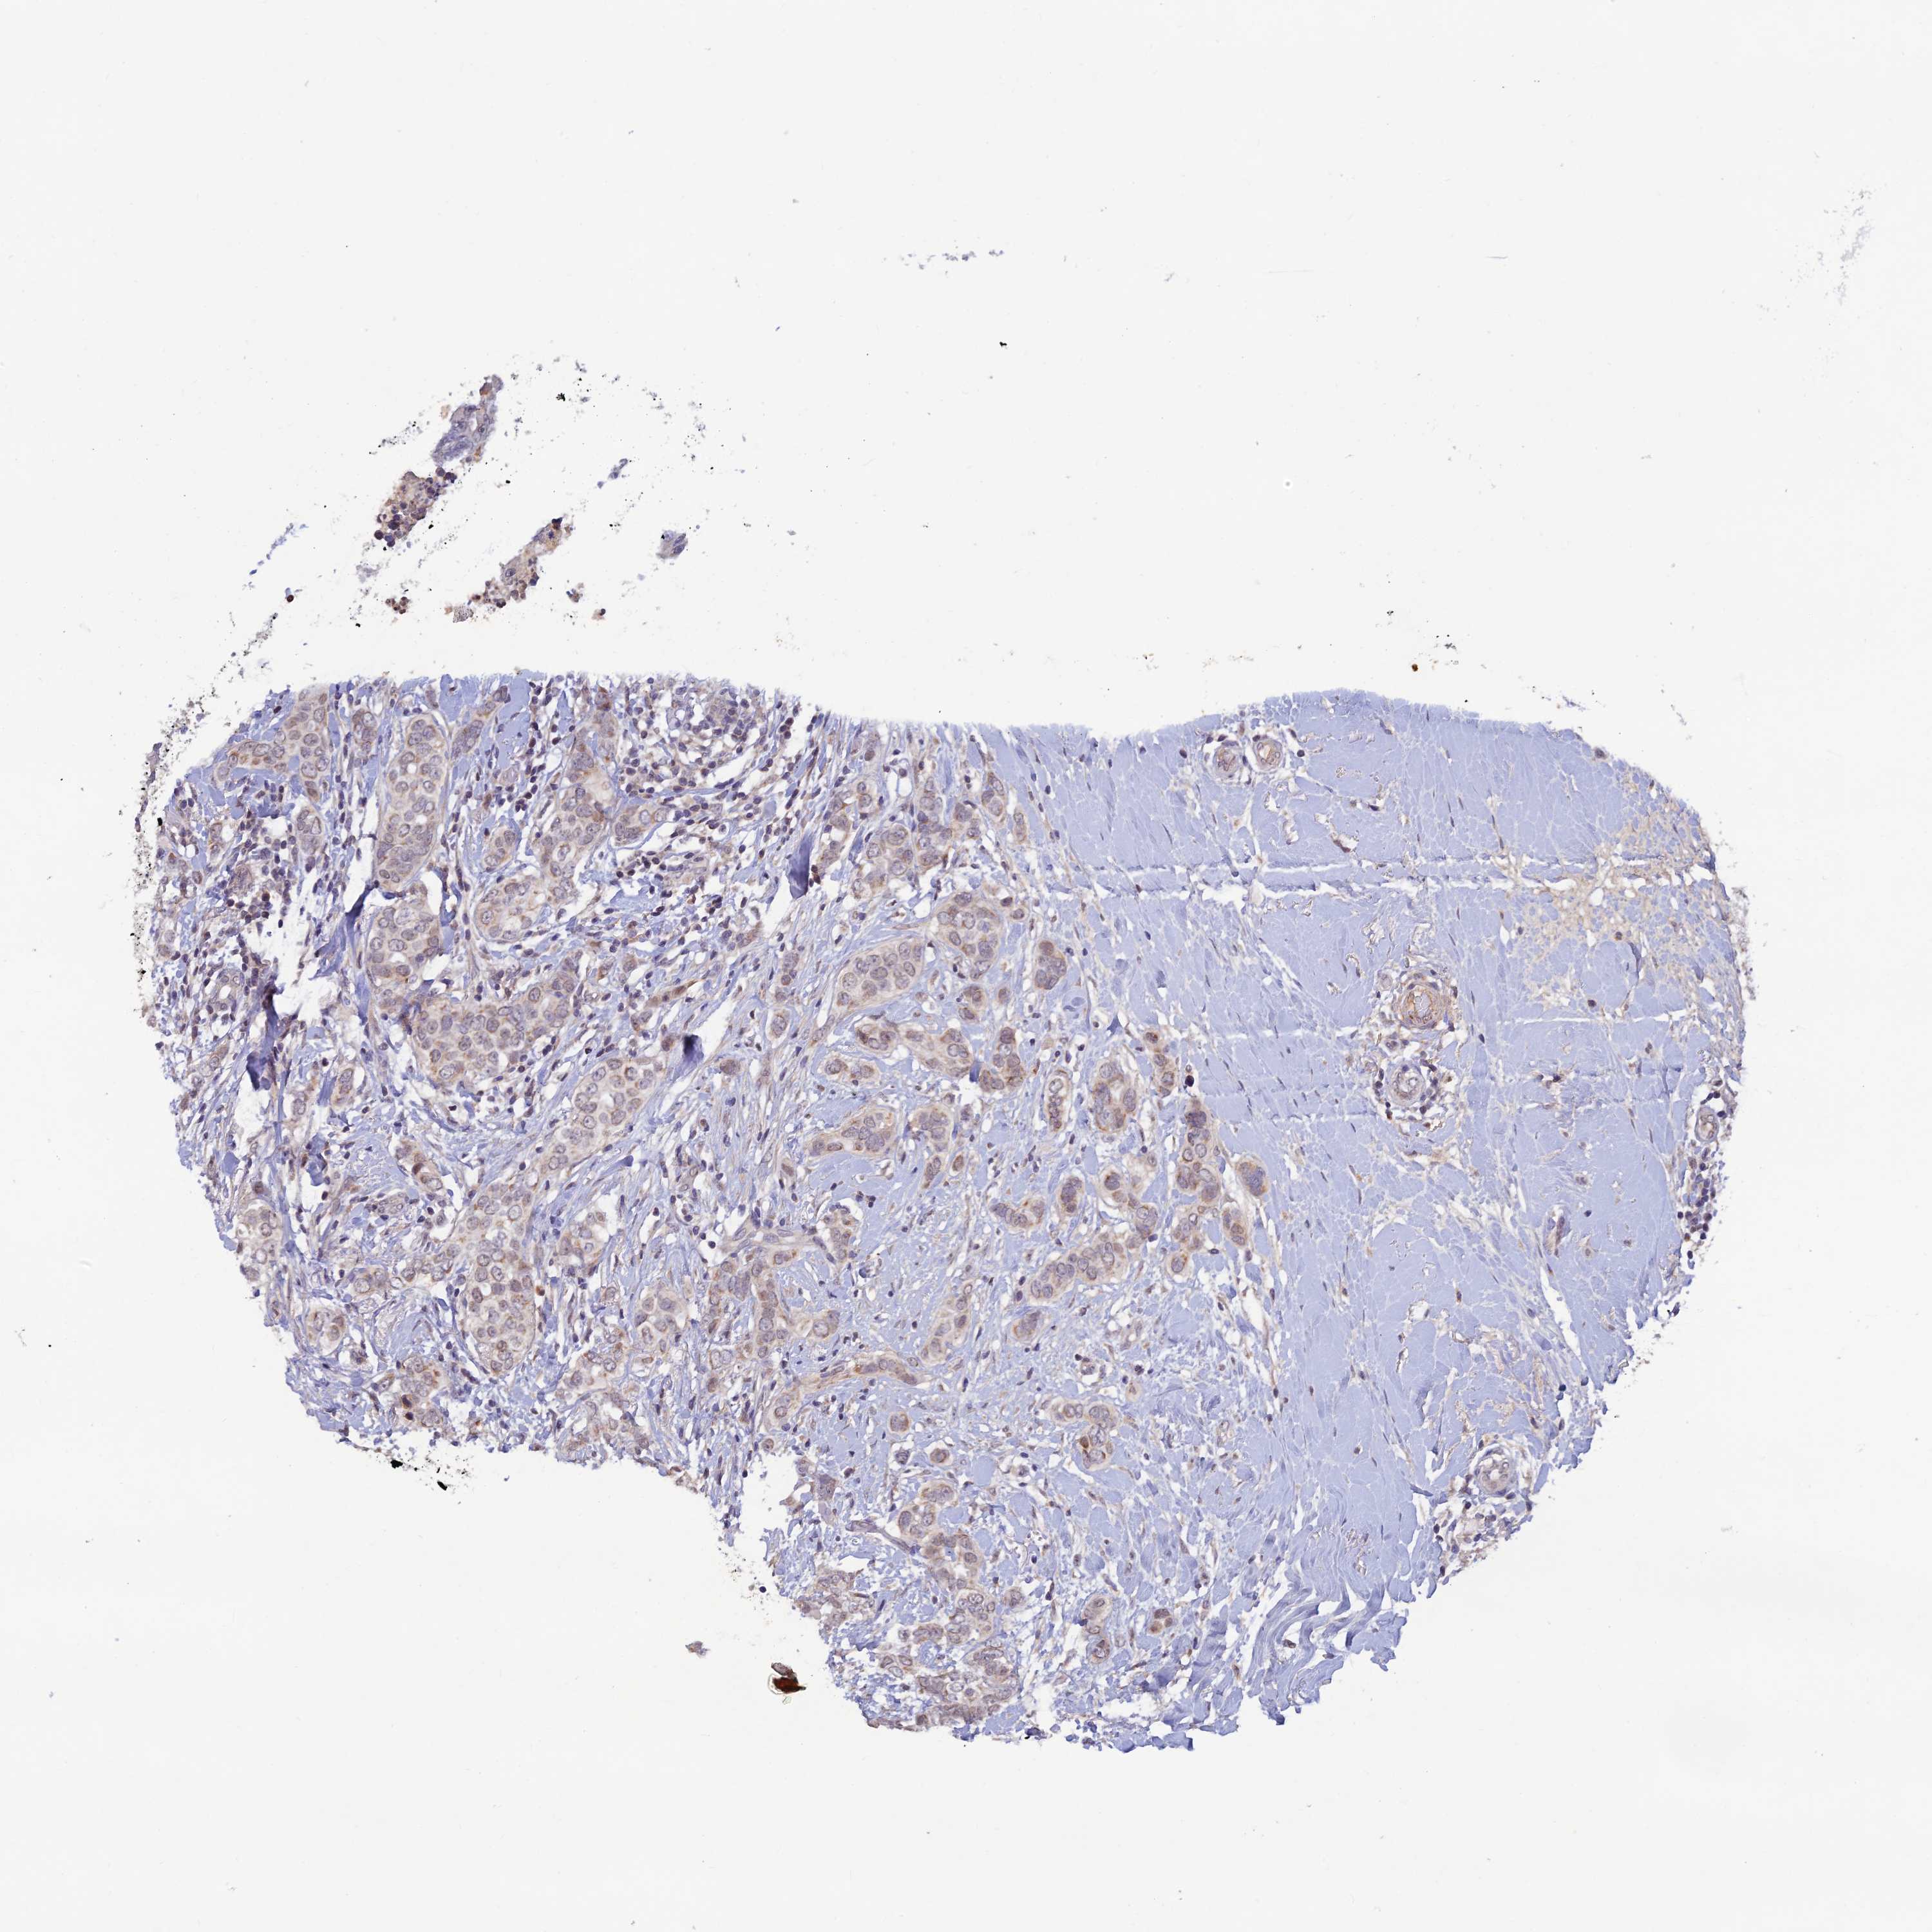

BRCA TCGA BRCA VALIDATION PROTEIN EXPRESSION

Breast cancer

Human cancer